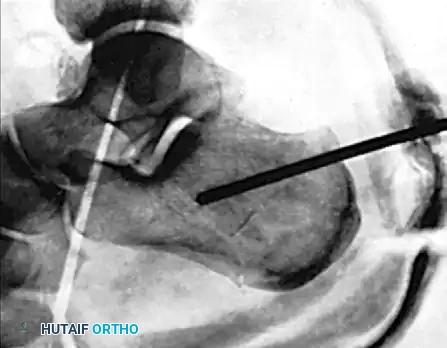

AXIAL FIXATION OF CALCANEAL FRACTURE Surgical Diagram

Figure 88-14A: Correct initial positioning and trajectory of the heavy Steinmann pin into the tongue fragment of the calcaneus.